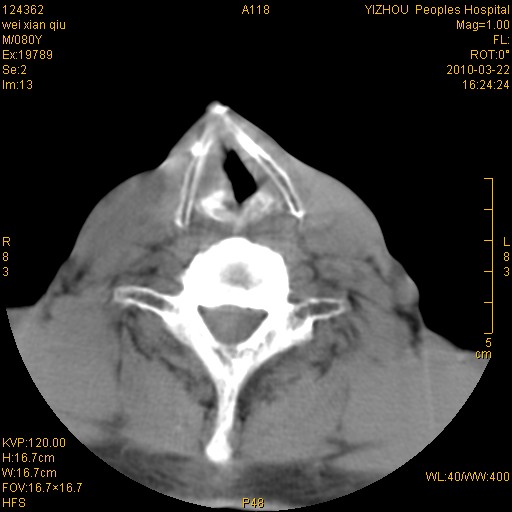

标题: CT25263:喉部占位?

男,80岁.声嘶三月余.

喉前庭右侧壁明显增厚,并见向内突出的软组织密度新生物,表面光滑,其后方软组织层次尚清晰,多考虑:喉部乳头状瘤!建议喉镜并病检!

右侧声们下区新生物